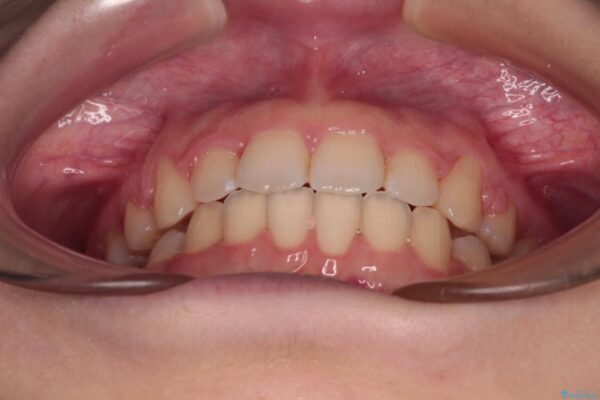

上下の前歯が突出しており、口が閉じにくいとのことで来院された患者様です。

上下前歯が著しく前突している状態であったので、上下左右の第1小臼歯4本を抜歯し、ワイヤー装置にて矯正治療を行うこととしました。

治療後